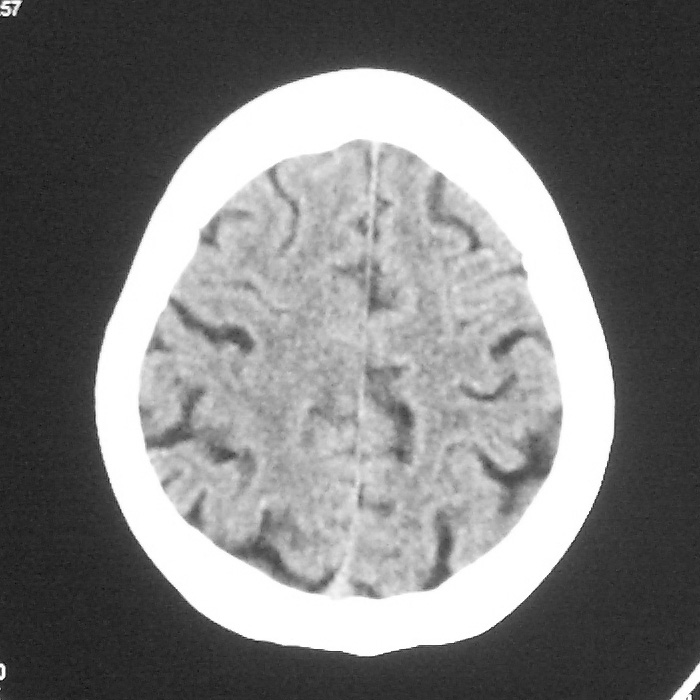

f,70y,口角歪斜、流涎、吐词不清三天

左侧大脑基底节区点状低密度影,边缘清楚,左侧腔梗或软化灶,没什么问题啊?

症状这么明显的话一般不会是单纯面神经麻痹引起的,最好做个mri,如果确实没有问题的话才能考虑面神经麻痹,毕竟这两种病的治疗和预后不一样,这个病人还有脑白质疏松。

左侧半卵圆中心腔梗应当比较明确,右侧基底节好象不明显,不好说,做个mri明确吧

双侧多发腔梗

右侧基底,左侧半卵圆中心腔梗

1、右侧基底,左侧半卵圆中心腔梗。2脑萎缩。

左侧腔隙性梗塞灶,脑萎缩。

左侧基底节区示点状低密度灶,边界清楚,密度均匀,余所示无著变。

意见:腔隙性脑梗塞(左基底节区)

各位老师,报告这么写可以吗?右侧我没有看出来。

左侧半卵圆中心,右侧基底节腔梗。再加个脑萎缩吧

双侧多发腔梗 脑萎缩